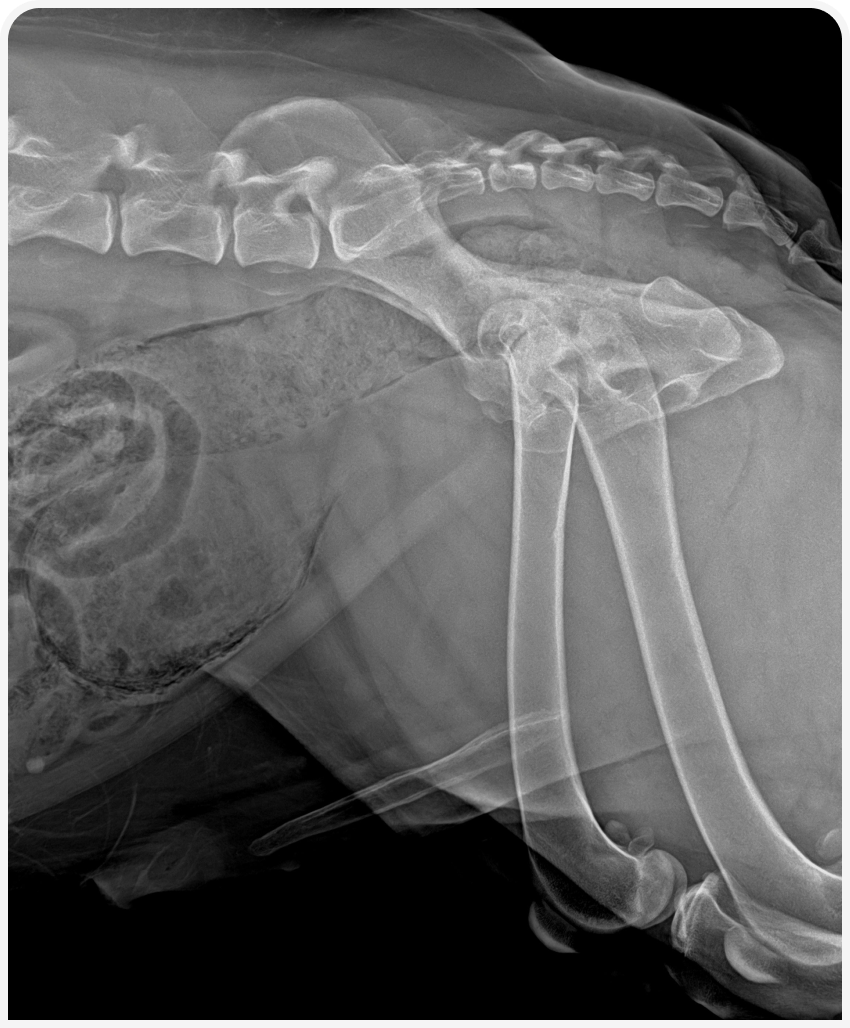

В ходе обследования мы можем обнаружить локальное скопление газа в стенке мочевого пузыря. А также столкнуться с трудностями в визуализации мочевого пузыря из-за тотального присутствия газа в стенках мочевого пузыря и артефактов изображения. Присутствие газа также может быть выявлено в уретре, из редка может быть выявлен газ в почечных лоханках и в тканях простаты у кобелей.

Рисунок 1. Рентгеновский снимок брюшной полости и области уретры в боковой проекции пациента с эмфизематозным циститом.